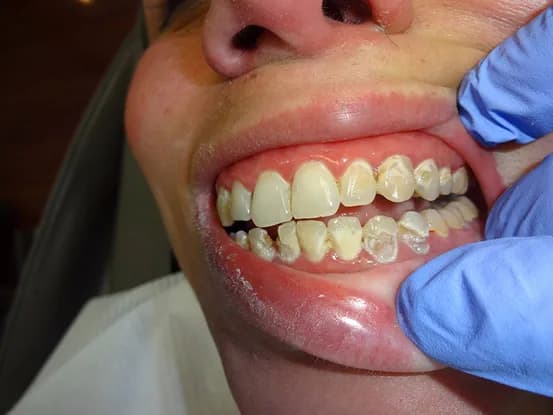

Case 7

38 year old female with extensive cervical caries from a high sugar diet and poor oral hygiene. 12 units of porcelain crowns and composite fillings to restore form and function followed by frequent recall visits